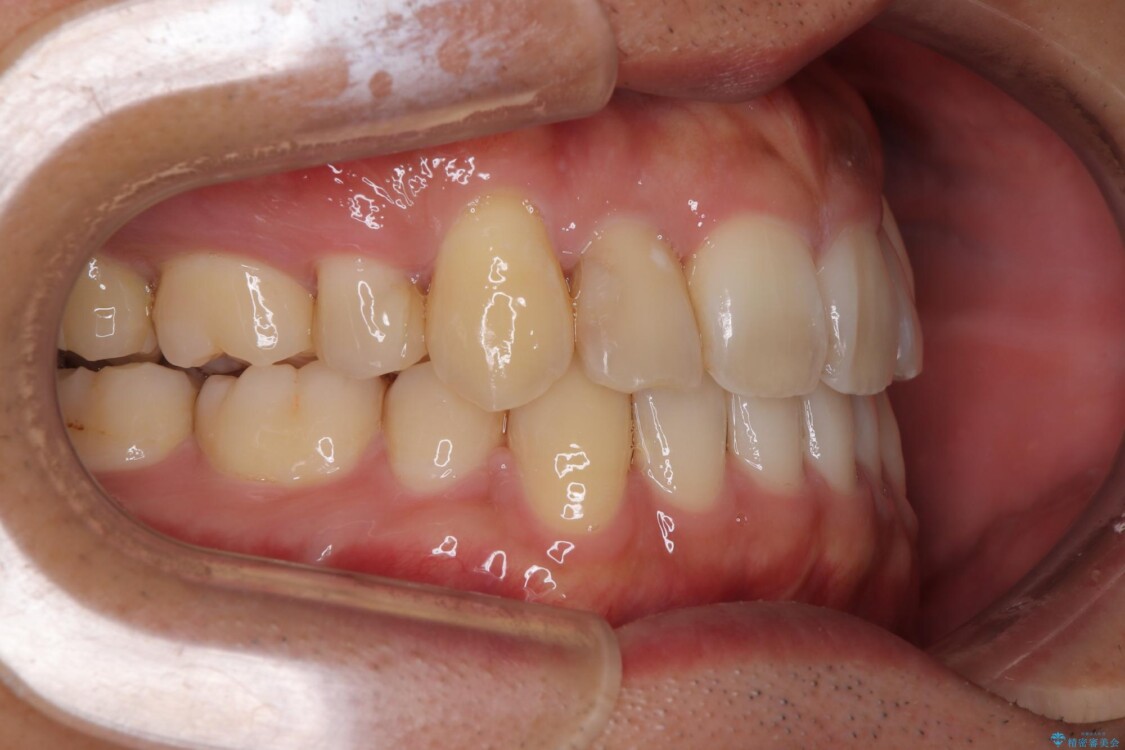

「八重歯を治したい」とご相談いただいた患者様の症例をご紹介します。

上下の前歯部に強い叢生(ガタガタの歯並び)があり、そのまま歯を並べると出っ歯になってしまう可能性がありました。

治療前

• 八重歯と前歯のガタガタを抜歯矯正で治療|クリアブラケット使用例 治療前画像